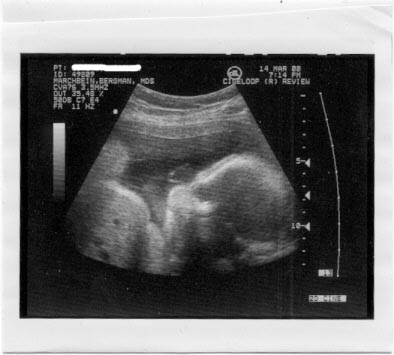

32 weeks 2 days

She is now 5 lbs 1 oz, Not sure how long